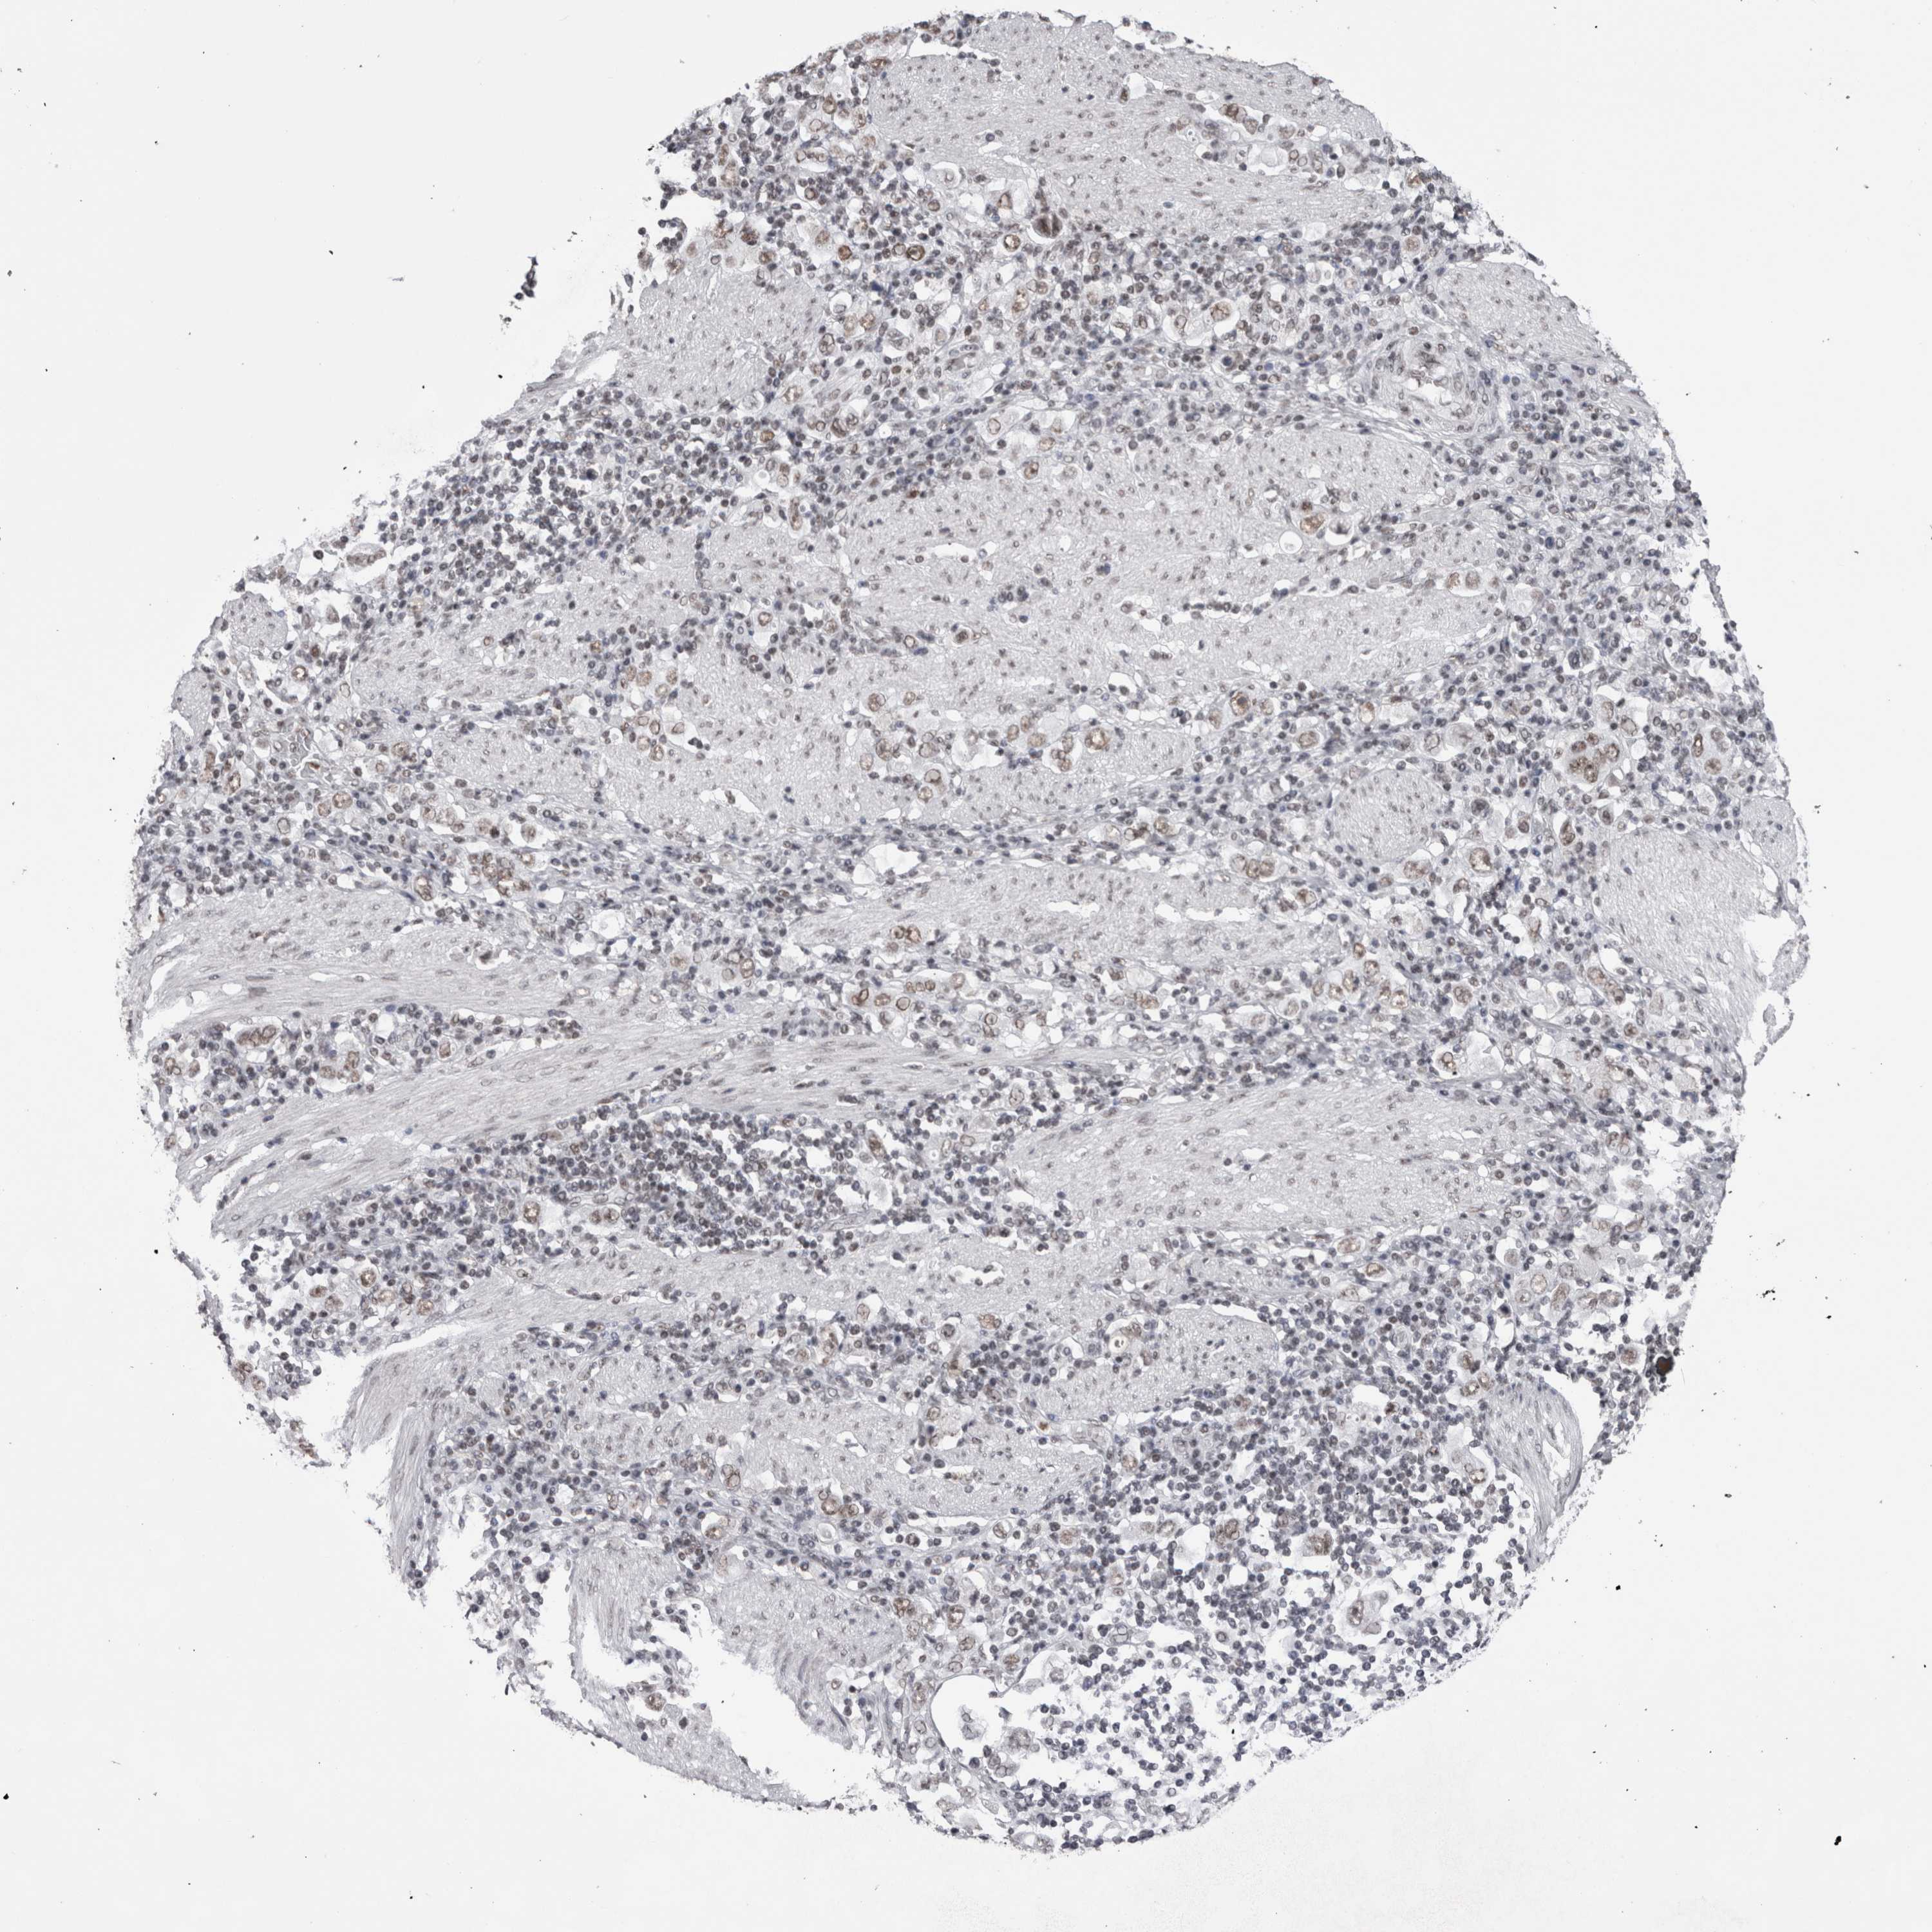

STOMACH CANCER - Protein expressioni

A mouse-over function shows sample information and annotation data. Click on an image to view it in a full screen mode. Samples can be filtered based on level of antibody staining by selecting one or several of the following categories: high, medium, low and not detected. The assay and annotation is described here.

Note that samples used for immunohistochemistry by the Human Protein Atlas do not correspond to samples in the TCGA dataset.

Antibody stainingi

Antibody staining in the annotated cell types in the current human tissue is reported as not detected, low, medium, or high, based on conventional immunohistochemistry profiling in selected tissues. This score is based on the combination of the staining intensity and fraction of stained cells.

Each image is clickable and will lead to virtual microscopy that enables deeper exploration of all samples and also displays staining intensity scores, fraction scores and subcellular localization as well as patient and tissue information for each sample.

Antibody CAB025404

Staining

High

Medium

Low

Not detected

Intensity

Strong

Moderate

Weak

Negative

Quantity

>75%

75%-25%

<25%

None

Location

Nuclear

Cytoplasmic/membranous

Cytoplasmic/membranous,nuclear

Adenocarcinoma, NOS